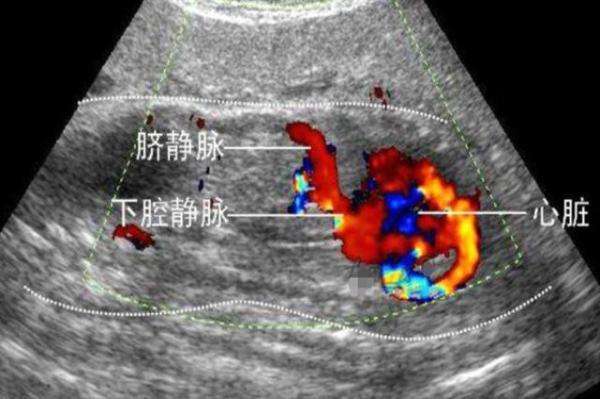

那么,我国目前的B超技术能够排出的畸形有哪些呢?国家对此也有规定,按照我国对于产检的管理办法,B超能够排除的六大畸形包括脑膨出、无脑儿、开放性脊柱裂、单腔心、胸腹壁缺损内脏外翻、致命性软骨发育不全等,而阿丽孩子的单肾状况确实不在检查能够排除的范围内。因此,按照法律规定,医院确实没有责任。

1、排畸B超并不能排除所有的畸形,就像我们上文中所说的,B超能排除的畸形主要有非常严重的那六种,以目前的技术水平,能够排除的胎儿畸形大约有百分之七十左右,还有百分之三十是无法检查出来的。例如,胎儿的视力、智力、运动以及听力等功能的异常是无法排除的,另外染色体的异常、手指或者是脚趾的数量以及轻微的唇裂等也是无法排除的。因为孩子在妈妈腹中的时候,大多数情况下都攥着拳头,因此很难看清楚。

3、胎儿的内脏B超能够看到的畸形是非常严重的结构畸形才能看出来,并且,看到的只是当时胎儿的状况。而像阿丽这样,在B超的时候能看到两个肾,但是在后期却发生了融合,那就无法预测到了。